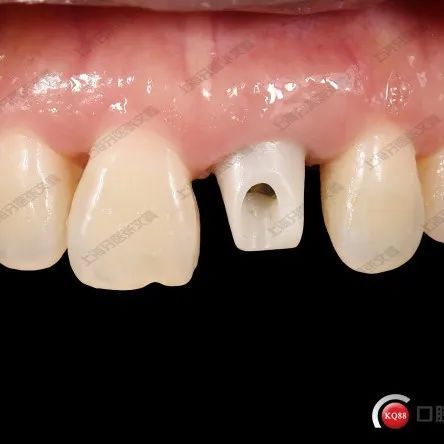

上颌门牙外伤即刻种植修复病例

今天跟大家分享一个上颌前门牙外伤即刻种植修复的病例。患者是一名女性,就诊前一天因为骑车摔倒导致唇部和牙齿外伤,当时去医院进行过外伤相关处理。外伤处理后第二天因牙齿疼痛,松动,无法咬合而就诊。当时口外检查,唇部肿胀非常严重,唇部有一处缝合线,唇部有血凝块结痂。口内检查21冠折,伴有牙髓外露。12、11和22可见牙齿隐裂,且有松动。患者因唇部肿胀伴有开口困难。当时这种情况因为患者情绪低落,所以没有拍摄就诊时的面部照片。...